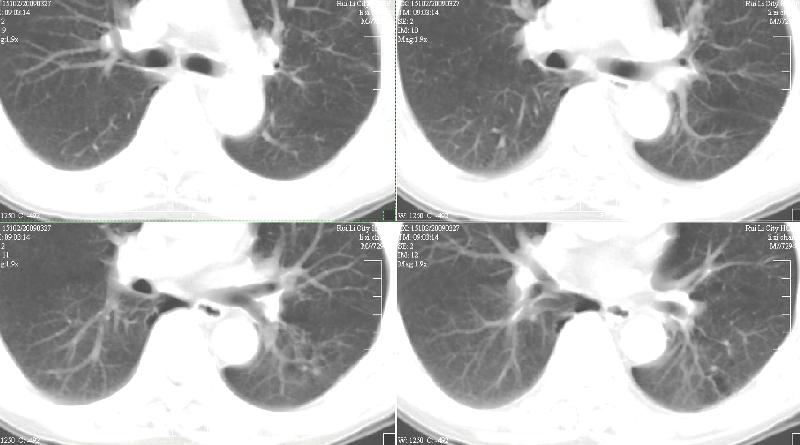

标题: CT19134:M,58岁。咳嗽痰多一月,不发热。 [打印本页]

标题: CT19134:M,58岁。咳嗽痰多一月,不发热。

ct:慢性支气管炎,(轻度泡性气肿),并左上叶尖后段结核球(可能大)。2、左下叶背段小片感染(考虑结核)